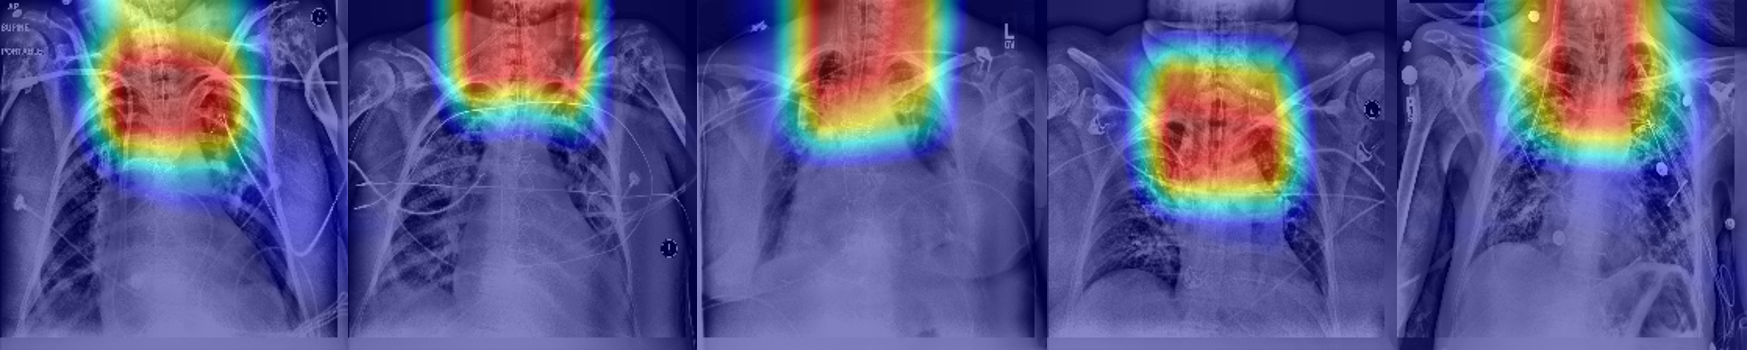

Refer to caption

Figure 7: Heatmap examples using ET tube classification CNN

We conducted an additional experiment using a different CNN architecture only for the classification task: identification of the tubes in real case scenarios. We trained a DenseNet [10] architecture with the same dataset we used in the second phase of the combined model - real cases with and without ET tube (n=7944) for 50 epochs and Adam optimizer. Training only for classification using a large real training data, we reached a high accuracy with an AUC of 0.975. Figure 7 shows a heatmap visualization of the last convolutional layer of the network. This visualization clearly indicates the localization on the ET tube area.